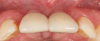

Fig 14. Final outcome at 1 year.

Figure 14

Fig 15. Clinical comparison of the volumetric gain obtained with the intervention, frontal views. Fig 15: Frontal view at baseline. Fig 16: Frontal view at 1-year post-treatment.

Figure 15

Fig 16. Clinical comparison of the volumetric gain obtained with the intervention, frontal views. Fig 15: Frontal view at baseline. Fig 16: Frontal view at 1-year post-treatment.

Figure 16

Figure 14 depicts the final outcome at 1 year (which can be compared to the pretreatment photograph in Figure 1). Figure 15 through Figure 18 show clinical comparisons of the outcome at baseline and 1 year, while Figure 19 and Figure 20 provide an ultrasonographic characterization of the soft tissue at baseline and 1 year. The facial probing depths at 1 year were 3-3-3 mm for implant No. 8 and 3-2-3 mm for implant No. 9. The patient was highly satisfied with the esthetic outcomes and overall treatment.